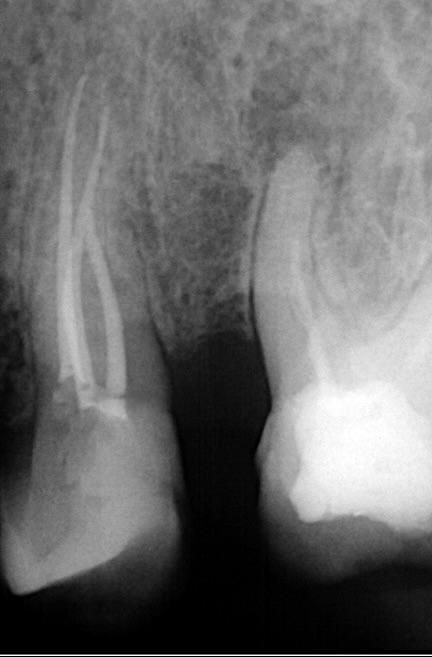

Obturation was completed with gutta-percha and CeraSeal bioceramic sealer, resulting in a stable, well-adapted three-dimensional seal.

Successful negotiation of the complex canal system was achieved following complete caries removal. Shaping with the DENCO Chameleon Dual Shaper enabled conservative, controlled preparation that fully respected the internal morphology and minimized pericervical dentin loss. A stable, three-dimensional seal was accomplished using gutta-percha and CeraSeal bioceramic sealer after a rigorous chemical disinfection protocol.